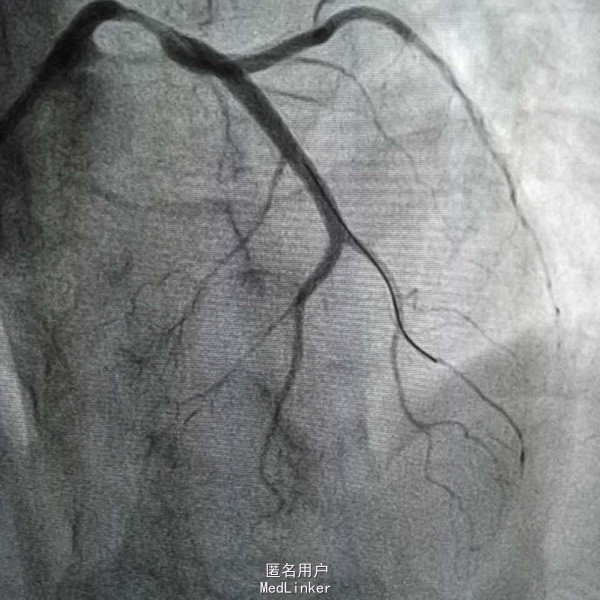

患者,女性,63岁,主因阵发性胸痛5天,加重15小时入院,既往否认高血压糖尿病史,无食物及药物过敏史,无不良嗜好。入院前一天剧烈胸痛晕厥一次,具体情况不详。

血压97/57mmHg,神清语明,口唇无发绀,颈静脉无怒张,双肺无啰音,心率82次每分,律齐,未闻及杂音,腹平软,肝脾未及,双下肢不肿。 辅查心电Il Ill avf ST段下移,avl V6 ST段抬高 白细胞14X109/L,D二聚体665ug/L,肌钙4.1ng/mL,

急性心肌梗死 心功能I级 处理,抗凝抗聚后行PCI治疗

造影示左主干闭塞,如图,预扩后快速送入支架行冠脉再通,此病人心电图很难判断左主干病变,值得警惕